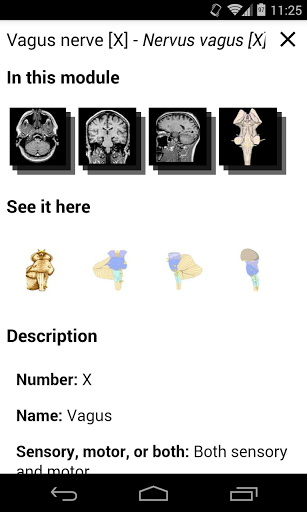

*Improved detail view of anatomical parts for easier identification in images of the current and other modules.

-In the details view of an anatomical structure related terms are now displayed

-Within the details view of an anatomical structure, a pin now points the related structure in all present images

Also tap directly on the image to navigate to the presented image in that module

- “Filter by”, in the details view you can now filter the images containing the anatomical structure by modality